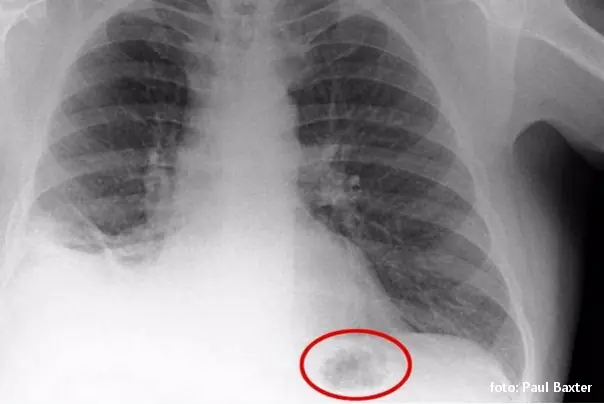

Lekari su prvobitno mislili da Pol, koji je takođe nedavno bolovao od upale pluća i bio je dugogodišnji pušač, ima tumor nakon što je rendgenski snimak pokazao masu u plućima.

Tokom bronhoskopije, lekari su identifikovali „nešto malo i narandžasto“ na dnu njegovog pluća, prema pisanju Britanskog medicinskog žurnala (BMJ).